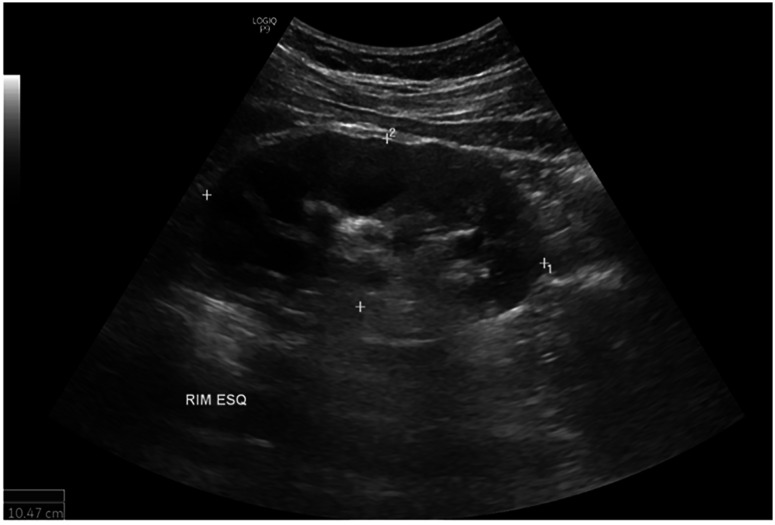

Urogenital tuberculosis (UGT) constitutes a significant extrapulmonary form of tuberculosis, often presenting non-specific symptoms and a prolonged indolent course that leads to delayed diagnosis and treatment, which can result in severe and irreversible complications such as urinary strictures, renal failure, and infertility. This report describes a case of a 38-year-old man with a five-month history of low back pain, hematuria, dysuria, and altered urinary frequency. Initial treatment for a presumed urinary tract infection failed, and subsequent diagnostic investigations showed stones, nodules, and cysts in his left kidney. A positive tuberculin skin test confirmed the diagnosis of UGT and identification of Mycobacterium tuberculosis in urine samples. The patient underwent standard six-month antituberculosis therapy and subsequent retreatment due to persistent symptoms. Despite significant symptom amelioration, irreversible urological sequelae, including infundibular stenosis, polyuria, and nocturia, remained. This case underscores the importance of early suspicion, accurate diagnosis, and timely treatment of UGT to minimize long-term complications. It also highlights the potential need for extended treatment length in complex cases to improve outcomes and reduce sequelae, warranting further research in this area.